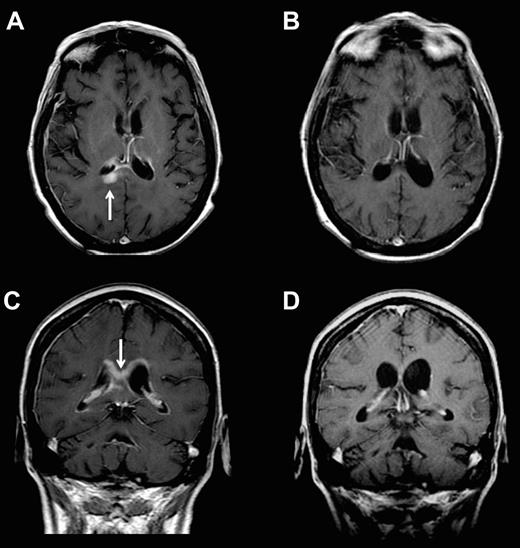

The overall CR rate in CSF and brain parenchyma was 43% and only 1 of the 6 patients who achieved cytologic and/or brain parenchymal CRs was treated with glucocorticoids during the month antecedent to pretreatment staging or during the course of protocol therapy. Complete regressions of parenchymal lesions within the temporal lobe and cerebral cortex and 1 PR within the corpus callosum were identified (Figure 3). In contrast, mixed responses were obtained in patients 1, 5, 6, and 13, in whom there was complete resolution of malignant cells in the CSF with simultaneous progression of bulky parenchymal disease that was documented by MRI at the week 5 restaging. After initial cytologic regressions during the first month of intraventricular therapy, patients 7 and 8 each developed new parenchymal lesions that were detected during the second month of the study.

Example of parenchymal response in a patient with refractory CNS lymphoma who was treated with intraventricular rituximab at 25 mg plus MTX. Panels A and C are baseline; panels B and D are after 4 weeks of therapy.